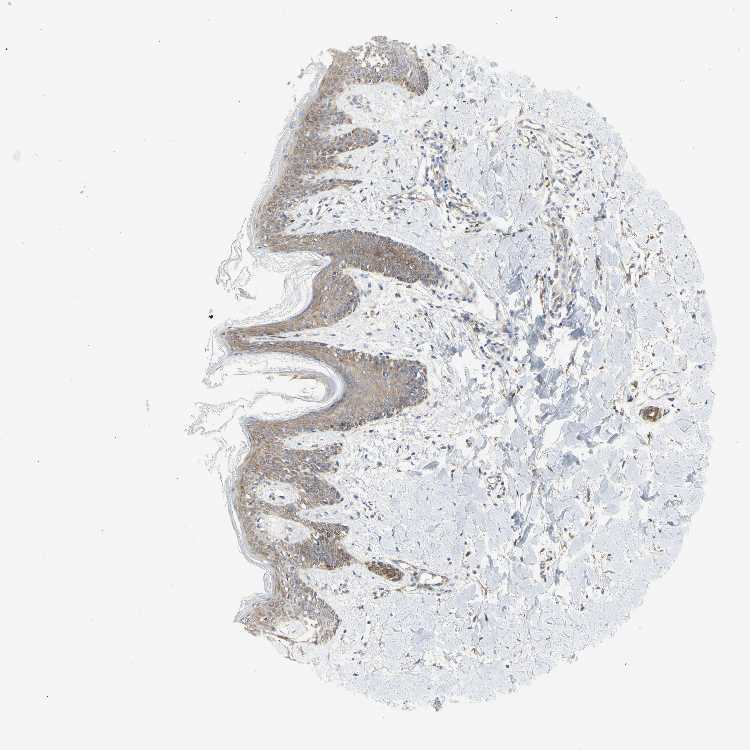

SKIN 1 - Antibody stainingi

Antibody staining in the annotated cell types in the current human tissue is reported as not detected, low, medium, or high, based on conventional immunohistochemistry profiling in selected tissues. This score is based on the combination of the staining intensity and fraction of stained cells.

Each image is clickable and will lead to virtual microscopy that enables deeper exploration of all samples and also displays staining intensity scores, fraction scores and subcellular localization as well as patient and tissue information for each sample.

Antibody HPA011252

Langerhans Medium

Fibroblasts Not detected

Keratinocytes Medium

Melanocytes Medium

SKIN 2 - Antibody stainingi

Epidermal cells Medium